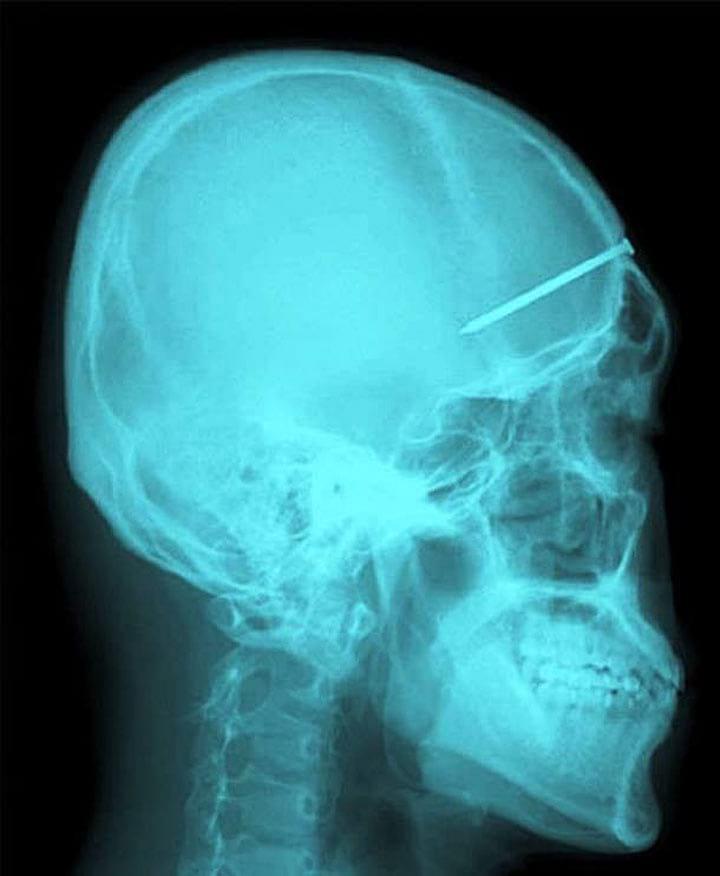

11. Храбрый парень помог предотвратить кражу в автобусе. Но получил ранение в голову. К счастью, он вскоре выздоровел. Добро не проходит бесследно

15. Стрела прошла через голову китайского мальчика. К счастью, он выжил

16. Хорошо, что он обратился в больницу. А то и не заметил бы, что у него гвоздь в голове